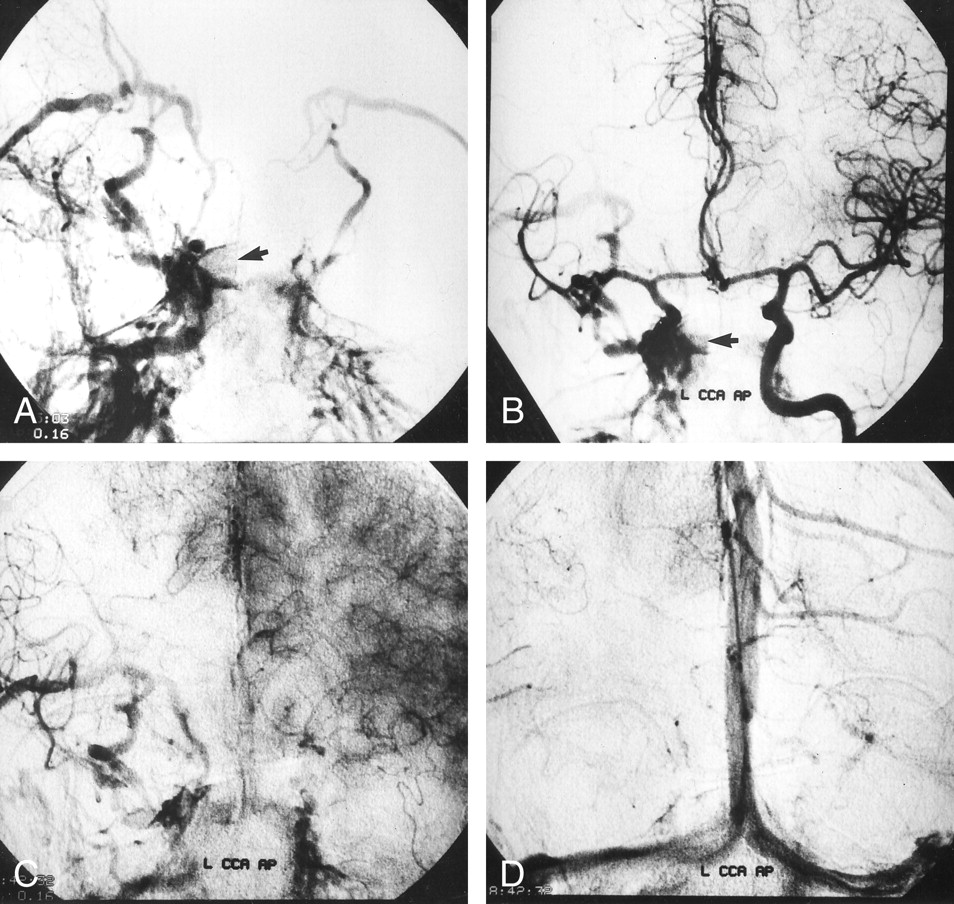

Angiograms obtained with external compression of the right CCA in a 58- year-old woman with iatrogenic right ICA injury associated with TSS.

A and B, Right (A) and left (B) CCA angiograms, anteroposterior projections, reveal contrast material extravasation within the sphenoid sinus (arrow) and show a high-flow CCF draining toward the superior ophthalmic vein, pterygoid plexus, and petrosal sinuses.

C and D, Left CCA angiograms reveal prominent circulation delays in the capillary (C) and venous (D) phases on the right side in comparison with the left side.

Standard cerebral angiography was performed with general anaesthesia by using a unilateral femoral approach. This examination revealed contrast material extravasation into the sphenoid sinus resulting from a laceration in the cavernous segment of the right ICA and a high-flow CCF with some retrograde cortical venous drainage (Fig 1A and B). Detachable balloon embolization was initially proposed; however, selective left ICA injection with external compression of the right common carotid artery resulted in a prominent delay (6-s delay) in the arterial, parenchymal, and venous phases in the right hemisphere (Fig 1C and D). Since the collateral circulation was not sufficient for balloon occlusion, we decided to attempt coronary stent-graft placement to treat the injury. A microcatheter (Rapid Transit-21; Cordis, Miami, FL) was passed through the injured segment of the ICA by using an angled guidewire (Terumo-16; Terumo, Tokyo, Japan). The microcatheter was then replaced with a 0.014-in exchange guidewire (Luge; Boston Scientific, Maple Grove, MN), and a Jostent coronary stent-graft (4 × 12 mm; Jomed International, Helsingborg, Sweden) was hand mounted onto a coronary angioplasty balloon (4-mm balloon diameter, 20-mm balloon length; Freeway, Jomed International). The Jostent covered stent-graft consisted of an ultrathin (75-μm) polytetrafluoroethylene graft material layered between two stents with reduced wall thickness. (The “CE” mark on this device certifies the manufacturer’s confirmation that the device satisfies both German and European safety and/or quality requirements.) The stent-graft and balloon were advanced to the injured segment of the ICA over the exchange guidewire that had been advanced into the right supraclinoid ICA (Fig 2A). The loaded balloon catheter was positioned at the level of the ICA injury. After a control angiogram was obtained, the stent-graft was inflated to 8 atm. The balloon was then deflated while negative pressure was applied, and the balloon was removed (Fig 2B). A repeat diagnostic arteriogram showed total closure of the lacerated portions of the ICA and CCF. Two spasmodic areas—one distal to the stent-graft and one at the cervical portion of the ICA—were noted (Fig 2C). These were assumed to be associated with irritation resulting from the advancement of the stent. Because spasm could have compromised the flow, 100 mg of a mixture of papaverine and isotonic sodium chloride solution was administered by means of manual injection. Upon completion of the procedure, the nasal hemorrhage ceased, and the patient was transferred to the intensive care unit. Follow-up arteriograms, obtained 3 mo after the patient was discharged, showed absent filling of the CCF, with normal patency of the ICA. The follow-up angiographic study showed no evidence of intimal hyperplasia or concomitant vessel stenosis (Fig 2D).